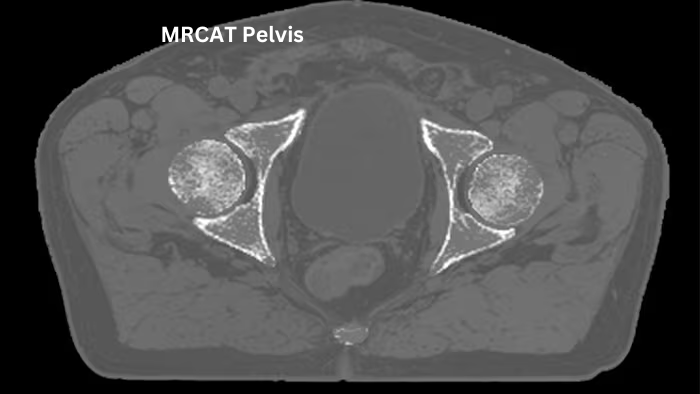

Compressed SENSE

Revolutionary acceleration technology that reduces the time for individual MRI sequences and entire MRI exams.